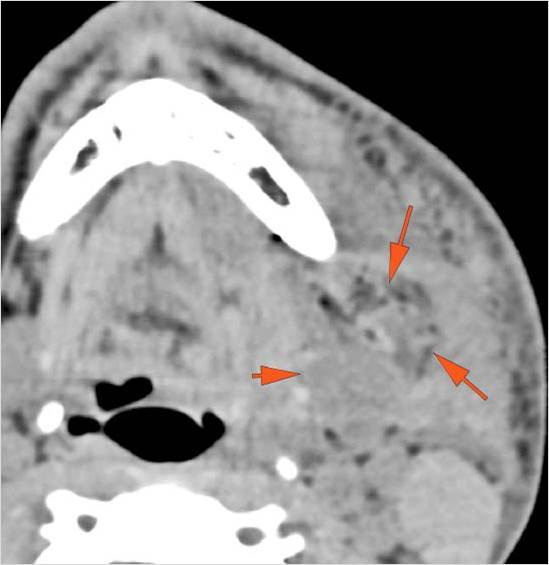

There is soft tissue swelling suggesting injury to the parotid or submandibular glands. [Yes/No]